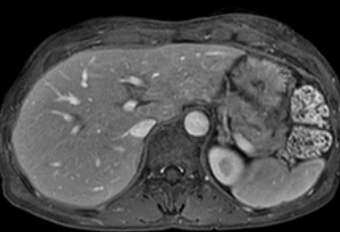

암전문의 김자영 원장이 암 환자의 수술 후 CT 결과에 대해 이야기했어요. 암(癌) 수술 후 CT에서 간전이나 폐전이, 수술 부위 주변 재발 등 생각지 못한 이상 소견을 볼 수 있음을 경험으로 언급했어요.

예를 들어, 대장암 환자의 경우 대장암 수술 후 CT에서 간전이가 발견되는 경우가 많으며, 이는 환자가 의사에게 의문을 제기하는 사례라고 언급했죠. 특히 최장암 환자들 사이에서 이러한 결과가 빈번히 나타날 수 있다고 설명했어요.

대장암 수술 후 간전이가 있는 경우, 대장부터 먼저 수술하고 이후 항암치료하는 경우도 있고, 나중에 간전이 된 부위를 수술할 수 있어요.

수술 후 CT 확인 시, 간전이가 크게 성장하거나 개수가 늘어날 수 있지만 이는 수술로 인한 강력한 염증 시그널로 인한 자연적인 반응이에요.

대장암 수술은 몸에 염증을 유발할 수 있지만, 이는 암세포 성장에 직접적인 연관이 있다기보다는 시그널에 반응하는 세포들이 빨리 성장할 수 있다는 것을 의미하는 거죠.

따라서 대장암 수술 자체가 암세포 성장을 촉진하는 것은 아니며, 갑자기 빠르게 암이 성장하는 것은 자연적인 반응이라는 점을 이해해야 해요.